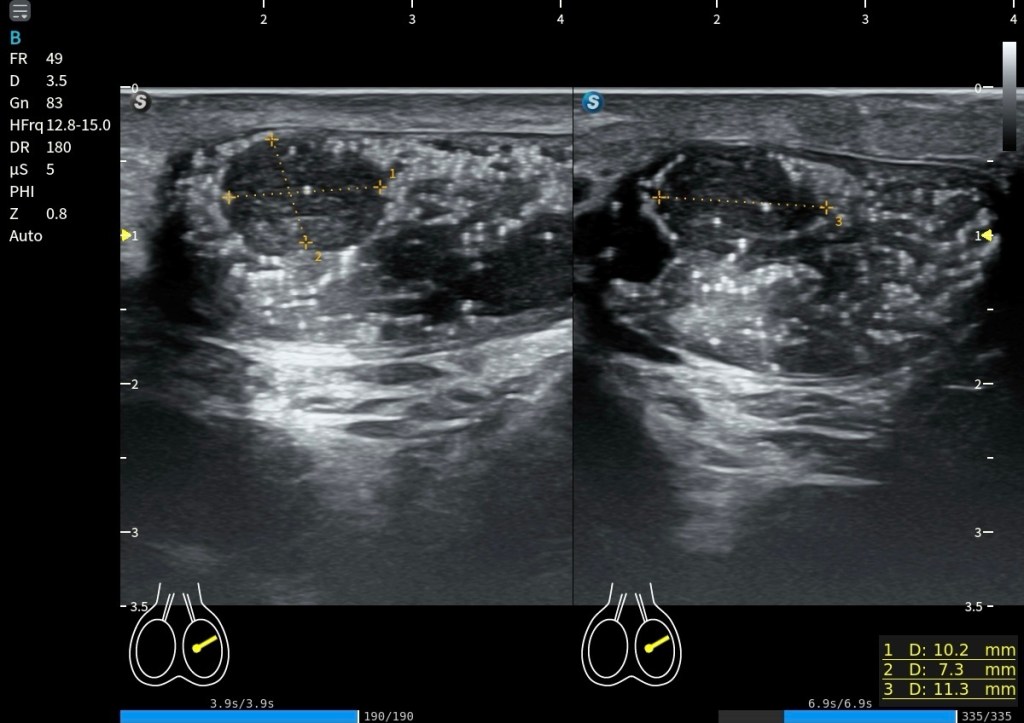

La alteración más habitual no es su ausencia, sino su cambio estructural con la edad. Las conocidas bandas platismales representan la manifestación clínica más frecuente. Estudios ecográficos han demostrado que estas bandas corresponden a un comportamiento dinámico real del músculo: durante la contracción, el grosor del platisma aumenta significativamente dentro de la banda (≈37,9%), mientras que en las zonas adyacentes puede incluso disminuir (≈20,3%) (Van der Lei et al., 2023). Esto refuerza la idea de que no se trata solo de un fenómeno estético, sino de una reorganización funcional del músculo y su interacción con la piel y la fascia.